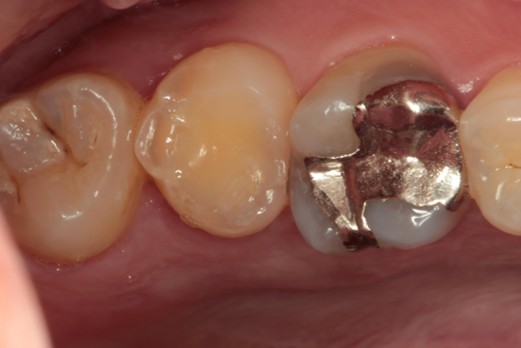

治療前

ご相談内容 |

奥歯に大きな穴が空いてる |

カウンセリング・診断結果 |

現在の歯の状態は保存が非常に難しく、これ以上無理に残すと周囲の健康な骨や隣の歯にまで悪影響を及ぼすリスクが高い状況です。 |